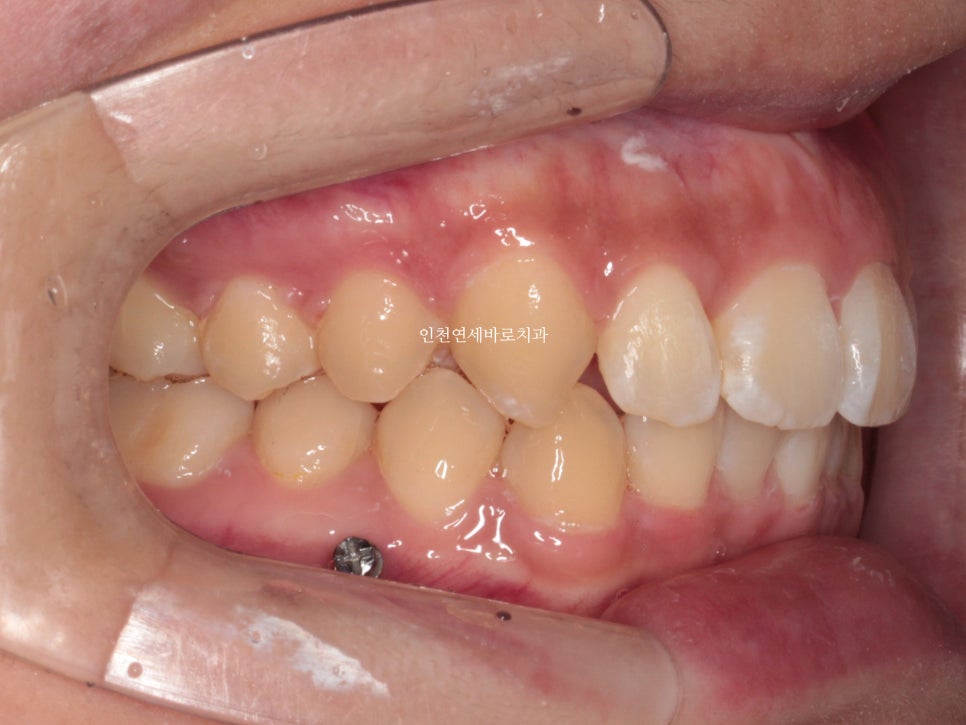

위아래 덧니가 있었고, 깊이 물리는 과개교합 및 중심선의 불일치 보이고 있습니다.

치료 후 1년이 지난 모습입니다.

중심선 및 교합 모두 잘 유지되고 있습니다.